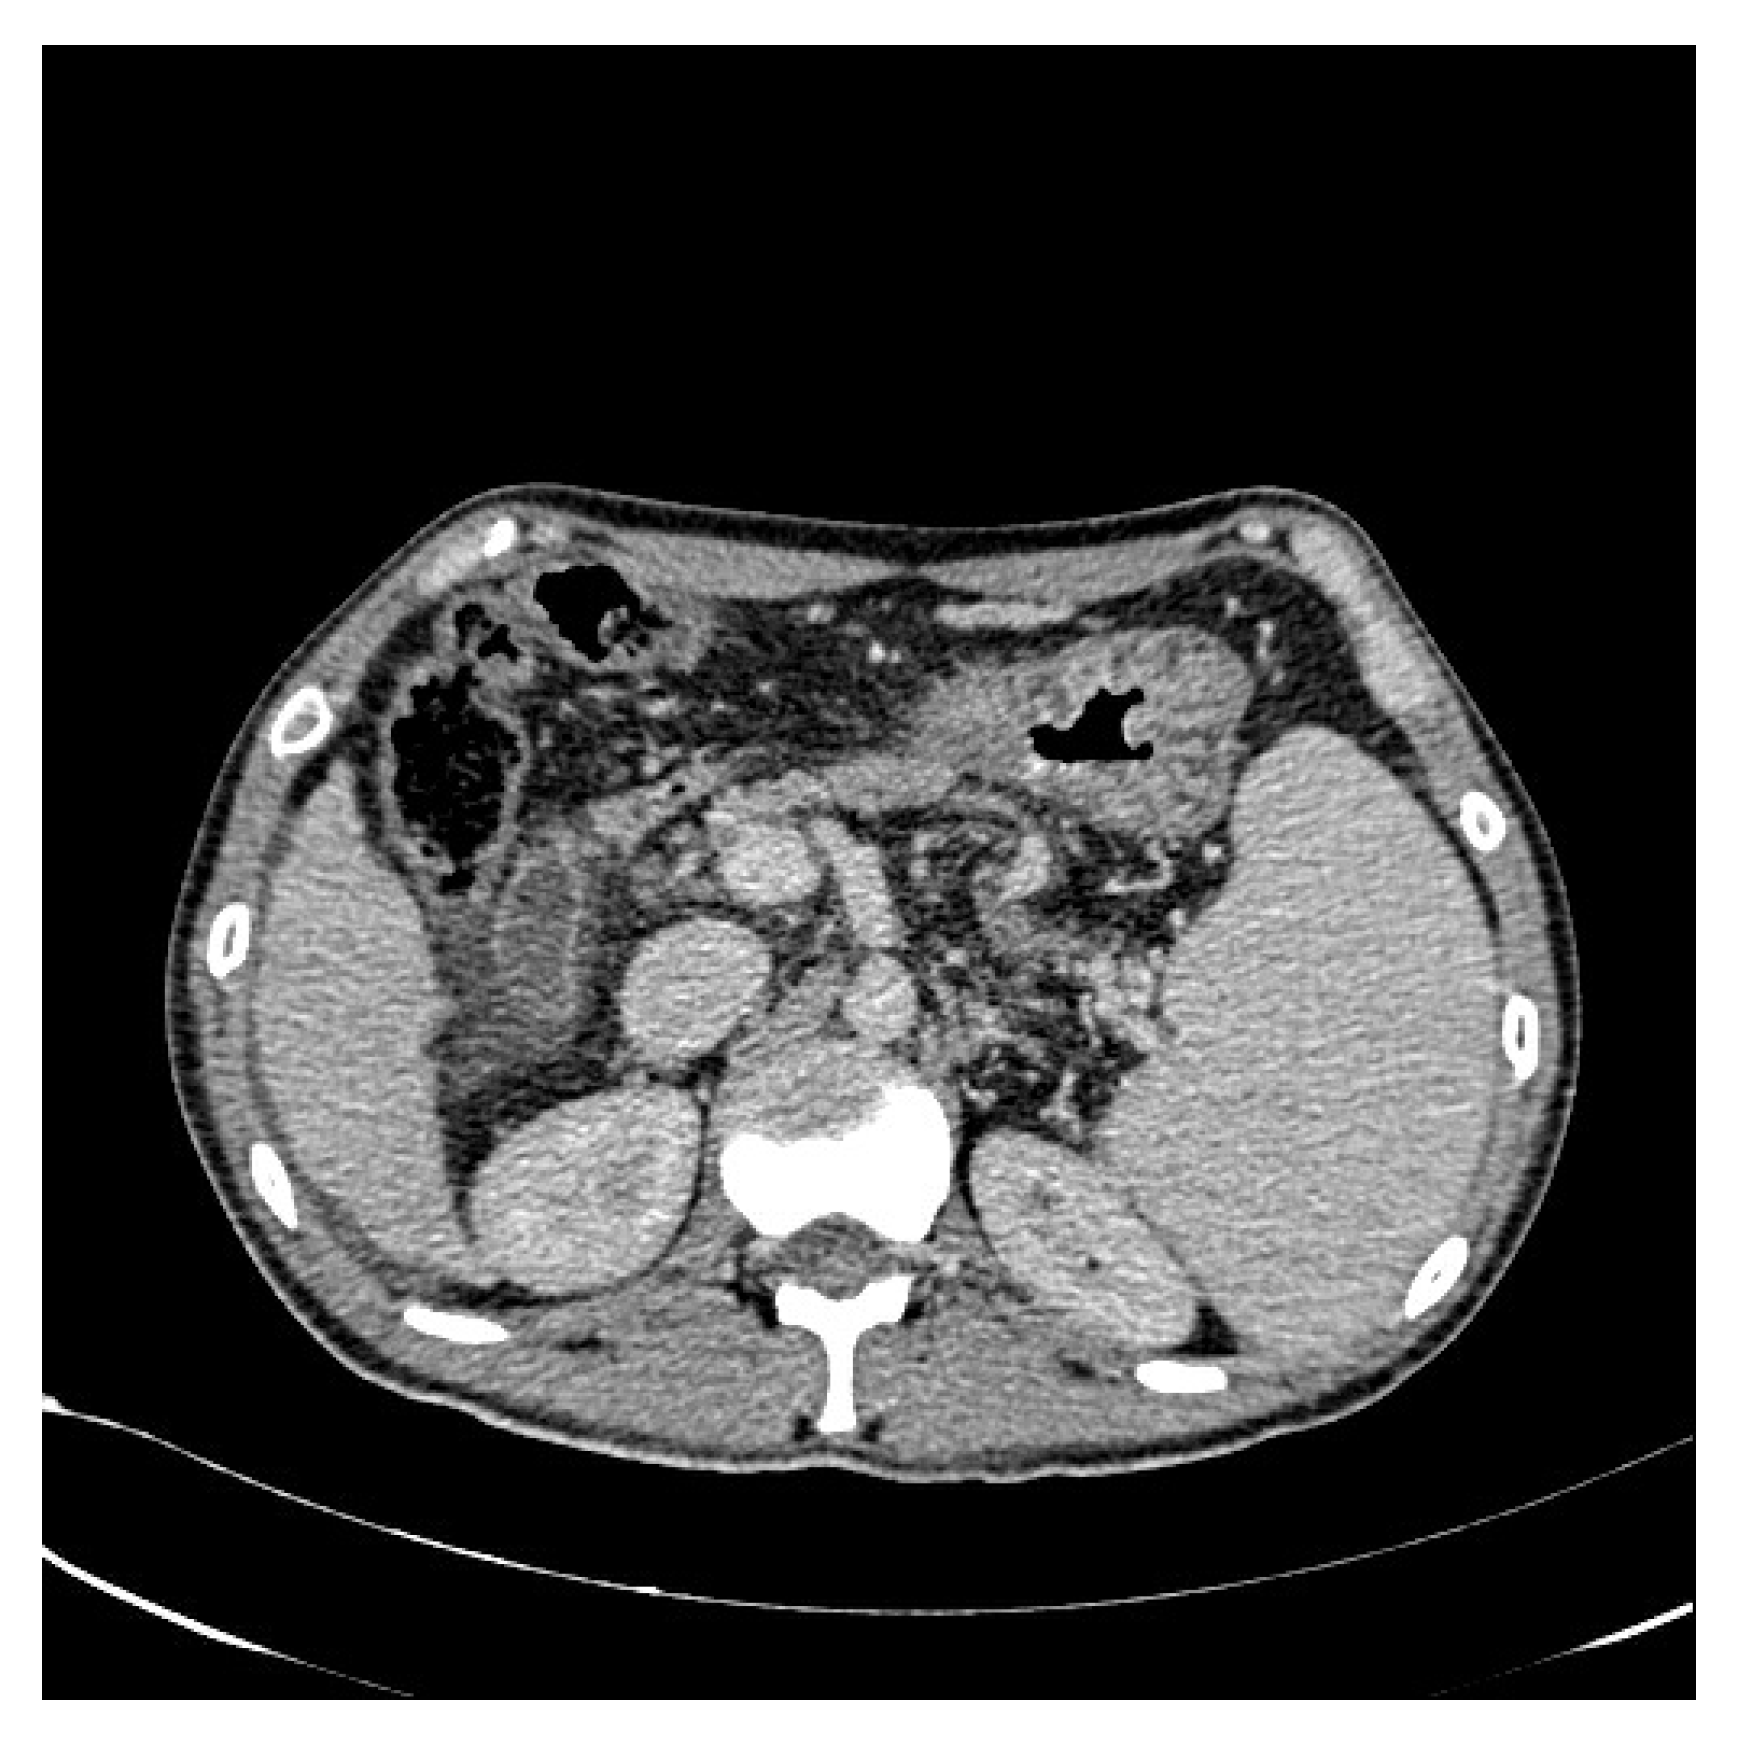

In addition, we used WGIF [38] to enhance the picture and obtain an image with stronger texture features to facilitate training after completion. Figure 3 and Figure 4 illustrate the comparison between the original and enhanced images, showcasing the augmentation of strong classification texture features. The original image, as depicted in Figure 3, demonstrates limited texture details and a relatively lower discriminative potential. However, upon applying advanced image enhancement techniques, as depicted in Figure 4, the texture features undergo substantial enrichment, resulting in heightened discriminative capabilities.

Figure 3.

Original CT image.